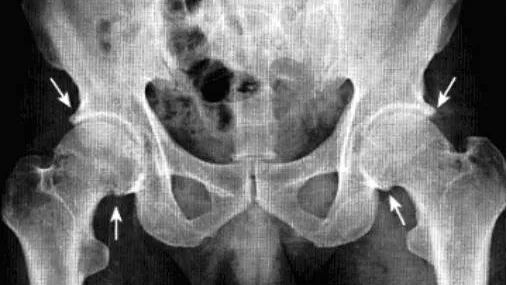

强直性脊柱炎累及髋关节

系累及中轴骨及近端大关节的血清阴性脊柱关节病。病变对称侵及骶髂关节、椎间小关节、附件韧带和近躯干的大关节,*后导致纤维性或骨性强直和畸形。髋关节是本病*常累及的关节,约占50*。

影像诊断:X线片为主要检查手段,MRI能显示早期髋关节改变。

1、平片:双侧对称受累,早期骨质疏松,关节囊膨隆,股骨头及髋臼骨质侵蚀糜烂;中期关节间隙一致性狭窄,软骨下囊性变,关节面边缘骨质增生,坐骨结节、坐骨耻骨支及股骨大转子可伴骨膜炎;晚期股骨头内移、髋臼内突,关节腔闭锁呈骨性强直。

2、CT:早期少量关节腔积液,可伴髂腰肌囊扩张,同时股骨头骨质疏松,股骨头及髋臼缘囊状、虫蚀状骨质缺损;中期关节面边缘硬化、囊变、骨赘形成,股骨头基底滑膜附着处增生,髋关节间隙均匀一致性狭窄消失,双侧髋对称性骨性强直,股骨头及髋臼可普遍性肥大。

3、MRI:①关节积液,关节间隙增宽,②滑膜增厚,增强后明显强化,③关节软骨水肿,④关节面软骨信号改变,炎性血管翳增生,信号强度不均,⑤软骨下囊性变,⑥关节骨性强直。